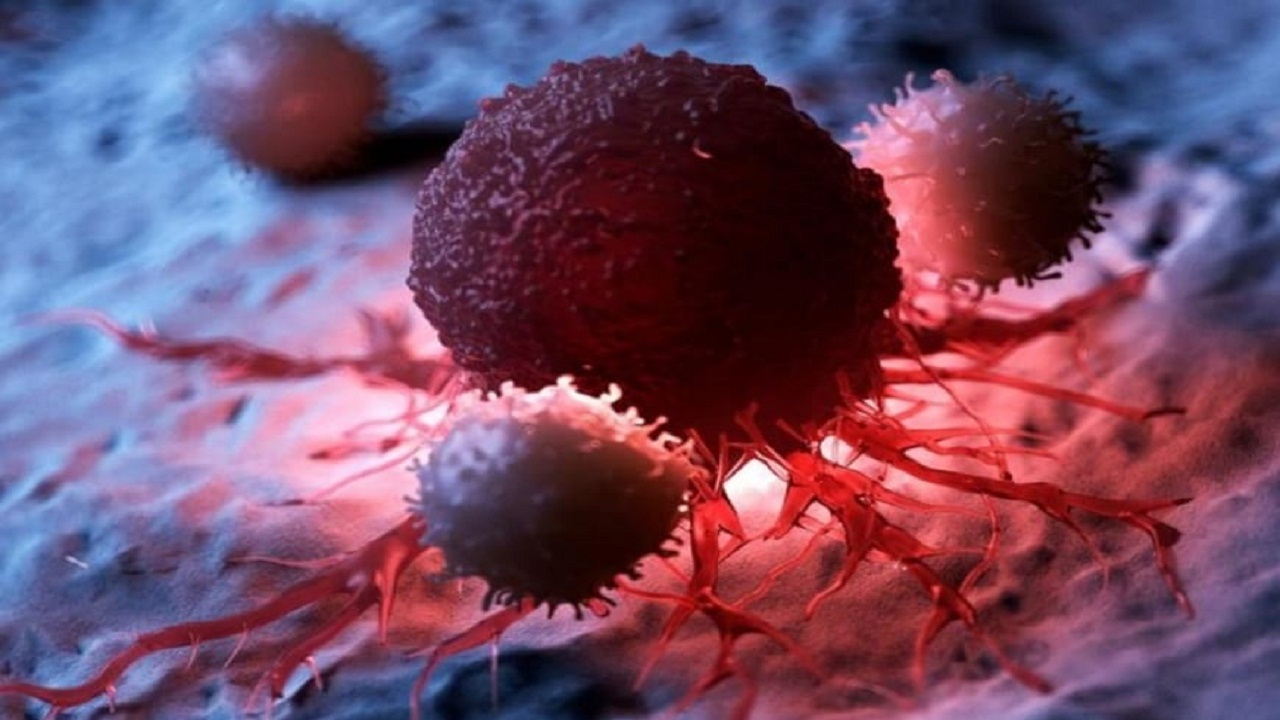

سرطان المستقيم

قائمة بالخضروات التي تحمي من سرطان القولون والمستقيم

بكتيريا خطيرة تكشف الإصابة بالسرطان

اكتشاف غير مسبوق أثبت نتائج مبهرة في علاج السرطان

تجمع الرياض الصحي الثاني: يمكن الوقاية من سرطان القولون والمستقيم